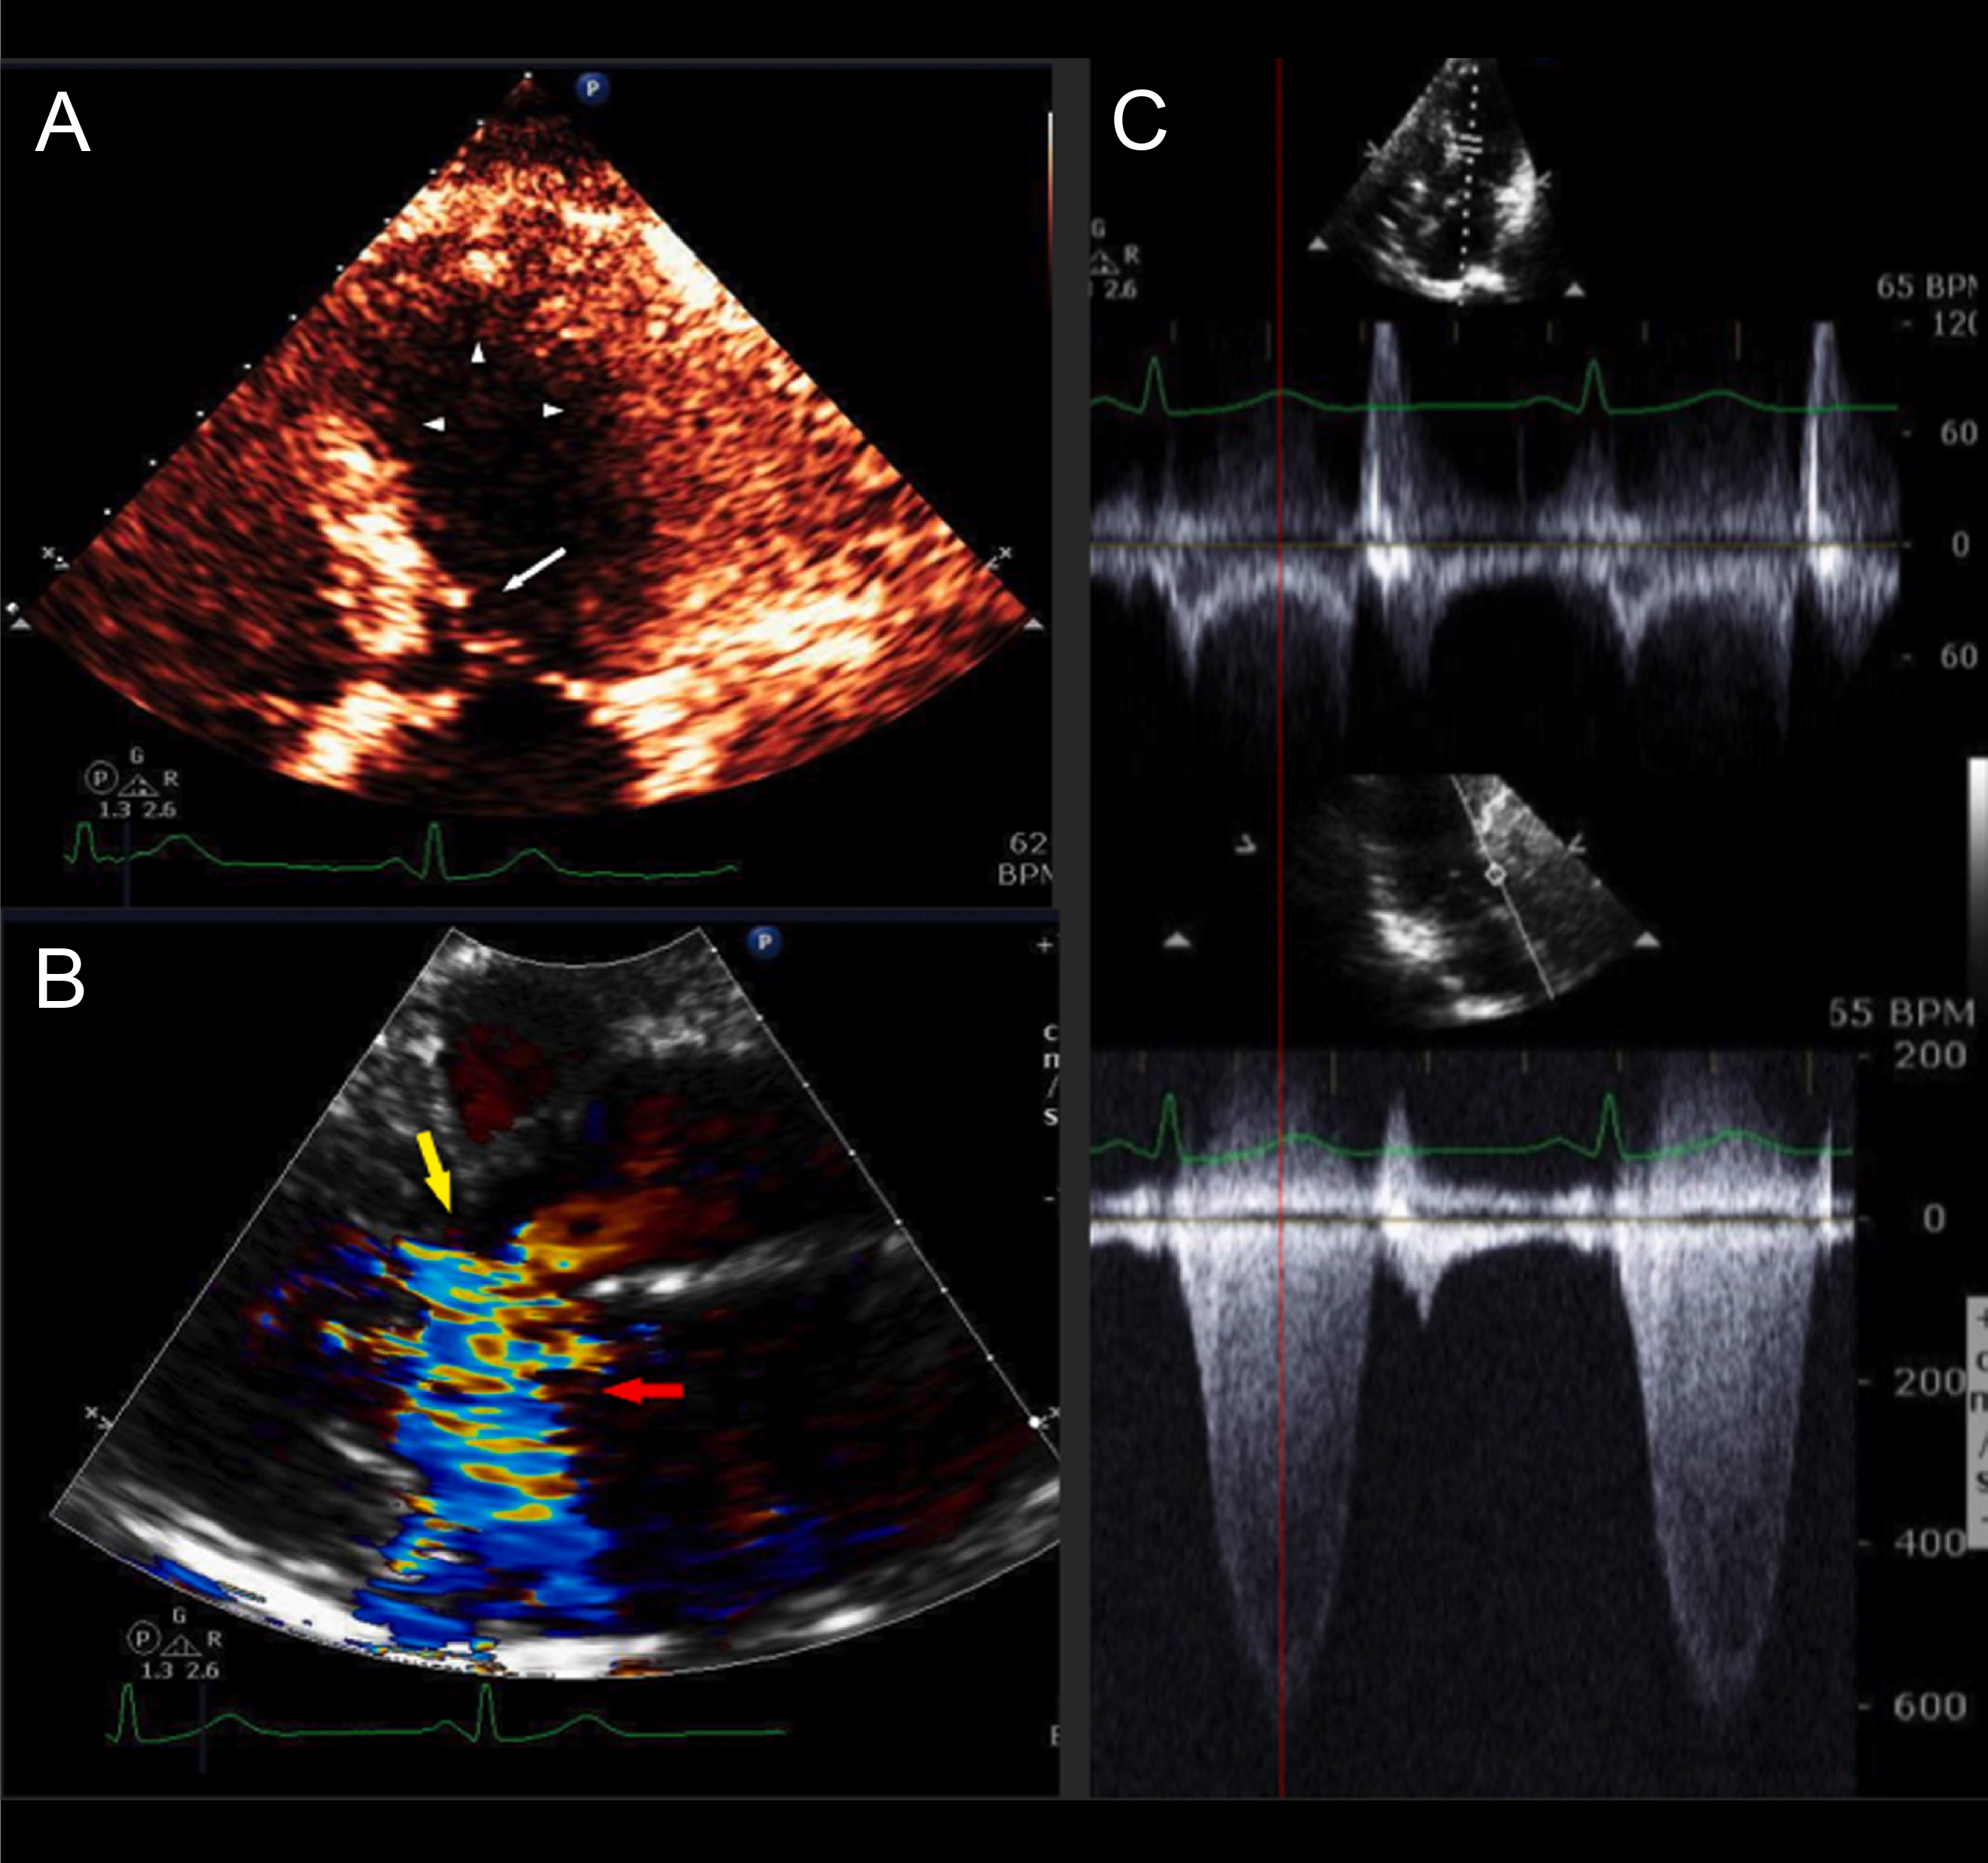

The clinical presentation of patients with obstructive HCM with LV ballooning share several overlapping features with TTS. Patients with these syndromes typically have chest pain, dyspnea, syncope, ST-segment changes on ECG, and elevated cardiac biomarkers, consistent with acute coronary syndrome (Fig. 3 (Ref. [9]) and Fig. 4) [7, 42]. The initial diagnostic workup for both conditions includes transthoracic echocardiogram (TTE), which typically shows apical hypokinesis with basal hyperkinesis. Coronary angiography excludes obstructive disease in both conditions [40].

Fig. 3.HCM with mild asymmetric septal hypertrophy, LVOT obstruction, and acute apical ballooning syndrome. A 63-year-old woman was admitted with near-syncope, hypotension, and NSTEMI (troponin I of 0.64 ng/mL). Coronary arteries were angiographically normal. LV cineangiography revealed acute apical ballooning. Left heart catheterization revealed an aortic pressure of 89/51 with a gradient of 100 mmHg. Following intravenous metoprolol, the patient’s outflow tract gradient improved to 40 mmHg, and her BP improved to 105/80 mmHg. A stress TTE performed 22 months after presentation demonstrated normal LV wall motion and no resting gradient. Following stress, TTE revealed mitral-septal contact and a peak LVOT gradient of 81 mmHg. This patient had very mild septal thickening HCM with acute apical ballooning due to LVOT obstruction presenting clinically as TTS. After recovery of LV systolic function, she continued to have severe LVOT gradients provocable after exercise. (A) Echocardiogram performed on admission (systolic frame) revealed apical and mid-LV ballooning with severe hypokinesis (arrowheads) and mitral-septal contact (white arrow). (B) Color Doppler (systolic frame) demonstrated severe mitral regurgitation (MR) (red arrow) and turbulence in the LV outflow tract (yellow arrow). (C) Pulsed-wave (PW; top) and continuous wave (CW; bottom) Doppler tracings obtained on admission TTE. PW Doppler at the level of the LVOT revealed a mid-systolic drop in PW Doppler velocities (“lobster claw abnormality”). The nadir in the drop of the PW Doppler corresponds to the peak of the CW gradient in the outflow tract (139 mmHg, bottom), as shown by the red dotted line. The PW velocity in mid-systole is low at 20 cm/sec, due to LV systolic dysfunction. Reproduced with permission Am J Cardiol [9]. HCM, hypertrophic cardiomyopathy; LVOT, left ventricular outflow tract; NSTEMI, Non-ST segment elevation myocardial infarction; LV, left ventricle; TTE, transthoracic echocardiogram; TTS takotsubo syndrome.

Fig. 4.Left heart catheterization and peak-to-peak pressure tracings of the patient described in Fig. 3, obtained using a retrograde pullback approach. (A) Pullback method for LV and aortic pressure tracings demonstrate a 60 mmHg gradient across the LVOT. (B) Aortic pressure tracings in the catheterization laboratory demonstrate a hypotensive patient with a systemic blood pressure of 87/51 mmHg. (C) Given the concern for acute apical ballooning due to severe LVOT obstruction in HCM, the patient was administered IV metoprolol 15 mg. Fifteen minutes later, aortic pressure tracings demonstrate improved systemic blood pressures to 110/60 mmHg, as well as an improved LVOT gradient to 40 mmHg. LV, left ventricle; LVOT, left ventricular outflow tract; HCM, hypertrophic cardiomyopathy; IV, intravenous.

Left heart catheterization with invasive hemodynamics is recommended in patients undergoing angiography for evaluation of acute apical ballooning to assess the severity and location of outflow tract obstruction. This is measured as the difference in peak pressure between the aorta and LV (Fig. 4). The presence of an LVOT gradient at rest, with Valsalva, or after premature ventricular contractions (PVC) is suggestive of LV ballooning from obstructive HCM. Its absence on the other hand suggests neurohumoral TTS, noting however that a subset of patients with TTS may have a low level of LVOT obstruction. A caveat is that LVOT gradients are dynamic and may subside in the hours after presentation due to LV systolic dysfunction. Standard Doppler echocardiography can under-diagnose and underestimate the severity of LV obstruction in patients with mid-LV obstructive HCM due to signal void from the absence or diminution of flow across the mid-left ventricle [13, 39]. In these instances, invasive hemodynamic measurements may detect the presence of high invasive catheterization gradients in the absence of high Doppler velocities [13, 39]. Alternatively, patients with a hypercontractile LV may generate high velocities on Doppler echocardiography due to complete LV emptying in the absence of true LV cavitary obstruction. This can be elucidated as the absence of a pressure gradient on cardiac catheterization [38].

The initial treatment of patients with HCM and acute apical ballooning is focused on identifying and reversing any triggers, including fluid resuscitation for hypovolemia and rhythm control for new arrhythmias [8]. Beta blockers form the mainstay of therapy in clinically stable cases [3]. In a previously published case series by our group, IV beta blockade (administered in the form of IV metoprolol or esmolol infusion) was found to be useful for reversing acute apical ballooning, even in HCM patients with borderline blood pressures [8] (Fig. 4). For patients with hypotension or shock, we recommend vasoconstrictive vasopressors such as phenylephrine for hemodynamic support, together with concomitant beta blockade for negative inotropy [8]. Vasopressors with inotropic properties and inotropic agents are contraindicated in these patients due to the risk of exacerbating LVOT obstruction [9].